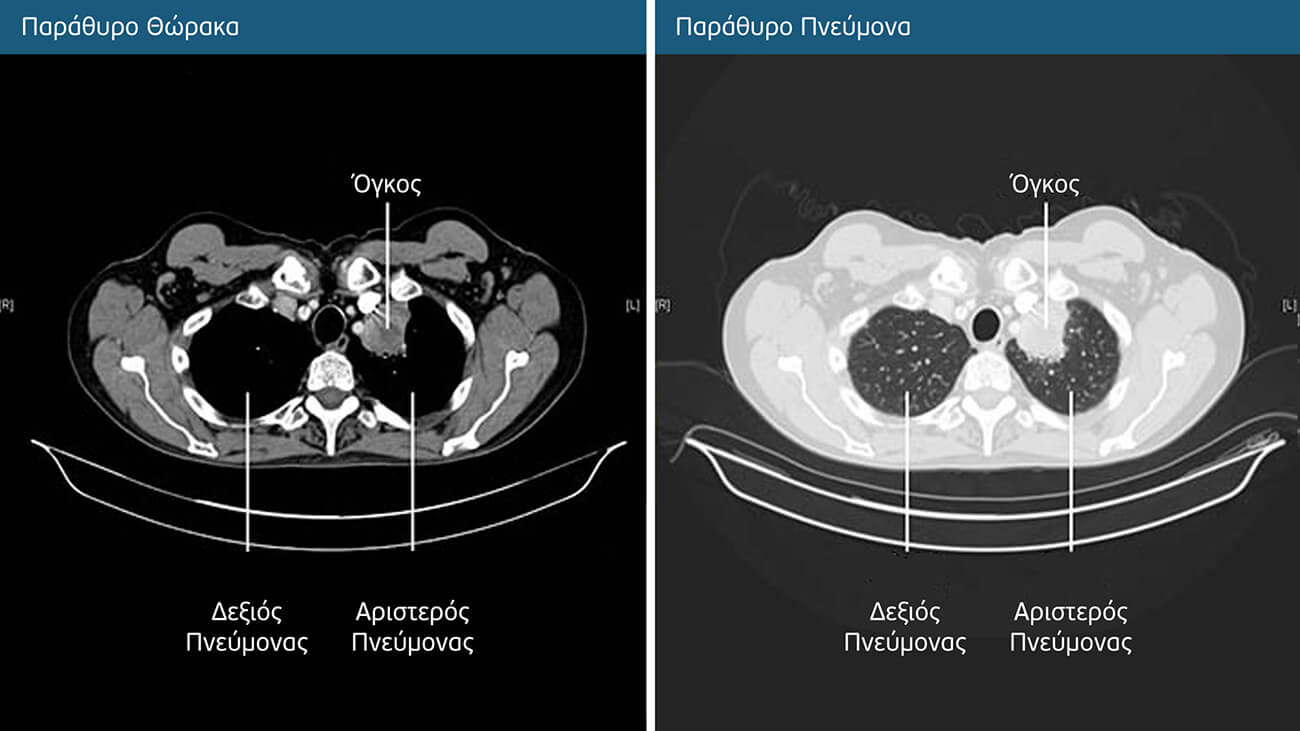

Αξονική ή Υπολογιστική Τομογραφία (CT) Θώρακος

Σε αντίθεση με τη συμβατική ακτινογραφία, η οποία λαμβάνει μία εικόνα, ο αξονικός τομογράφος λαμβάνει πολλαπλές εικόνες καθώς περιστρέφεται γύρω από τον ασθενή, προκειμένου να ληφθούν εικόνες από διαφορετικές γωνίες. Έτσι δημιουργούνται τρισδιάστατες (3D) απεικονίσεις των οργάνων και των ιστών.

Η αξονική τομογραφία μας δίνει συγκεκριμένες πληροφορίες σχετικά με το μέγεθος, το σχήμα και τη θέση των πνευμονικών μαζών ή όζων. Βοηθά επίσης στην ανεύρεση διογκωμένων λεμφαδένων ή μαζών σε άλλα όργανα που μπορεί να οφείλονται στην εξάπλωση του καρκίνου του πνεύμονα. Πρέπει να επισημάνουμε ότι, ενώ η αξονική τομογραφία μπορεί να δείξει ότι υπάρχει ένας συμπαγής όγκος, δεν μπορεί να καθορίσει επακριβώς τη φύση του, ούτε τη βιολογική συμπεριφορά του (πχ κακοήθης ή καλοήθης). Για τον σκοπό αυτό, απαιτούνται κατά κύριο λόγο ιστολογικές εξετάσεις (βιοψίες).

Ενίοτε πριν από την εξέταση χορηγείται στον ασθενή σκιαγραφικό υλικό είτε ως πόσιμο διάλυμα είτε ενδοφλέβια, έτσι ώστε ορισμένα όργανα και αιμοφόρα αγγεία να είναι ευδιάκριτα και να είναι η εξέταση πιο κατατοπιστική. Κατά τη διάρκεια της λήψης που διαρκεί μονάχα ελάχιστα δευτερόλεπτα, ο ασθενής πρέπει να παραμένει ακίνητος και να κρατήσει την αναπνοή του.

Σήμερα, χρησιμοποιούμε ευρέως την αξονική τομογραφία χαμηλής δόσης ακτινοβολίας (LDCT) για την προληπτική ανίχνευση καρκίνου του πνεύμονα και για την παρακολούθηση των μεταβολών στους πνευμονικούς όζους. Η δόση ακτινοβολίας της LDCT είναι πέντε φορές χαμηλότερη από εκείνη της συμβατικής αξονικής τομογραφίας.